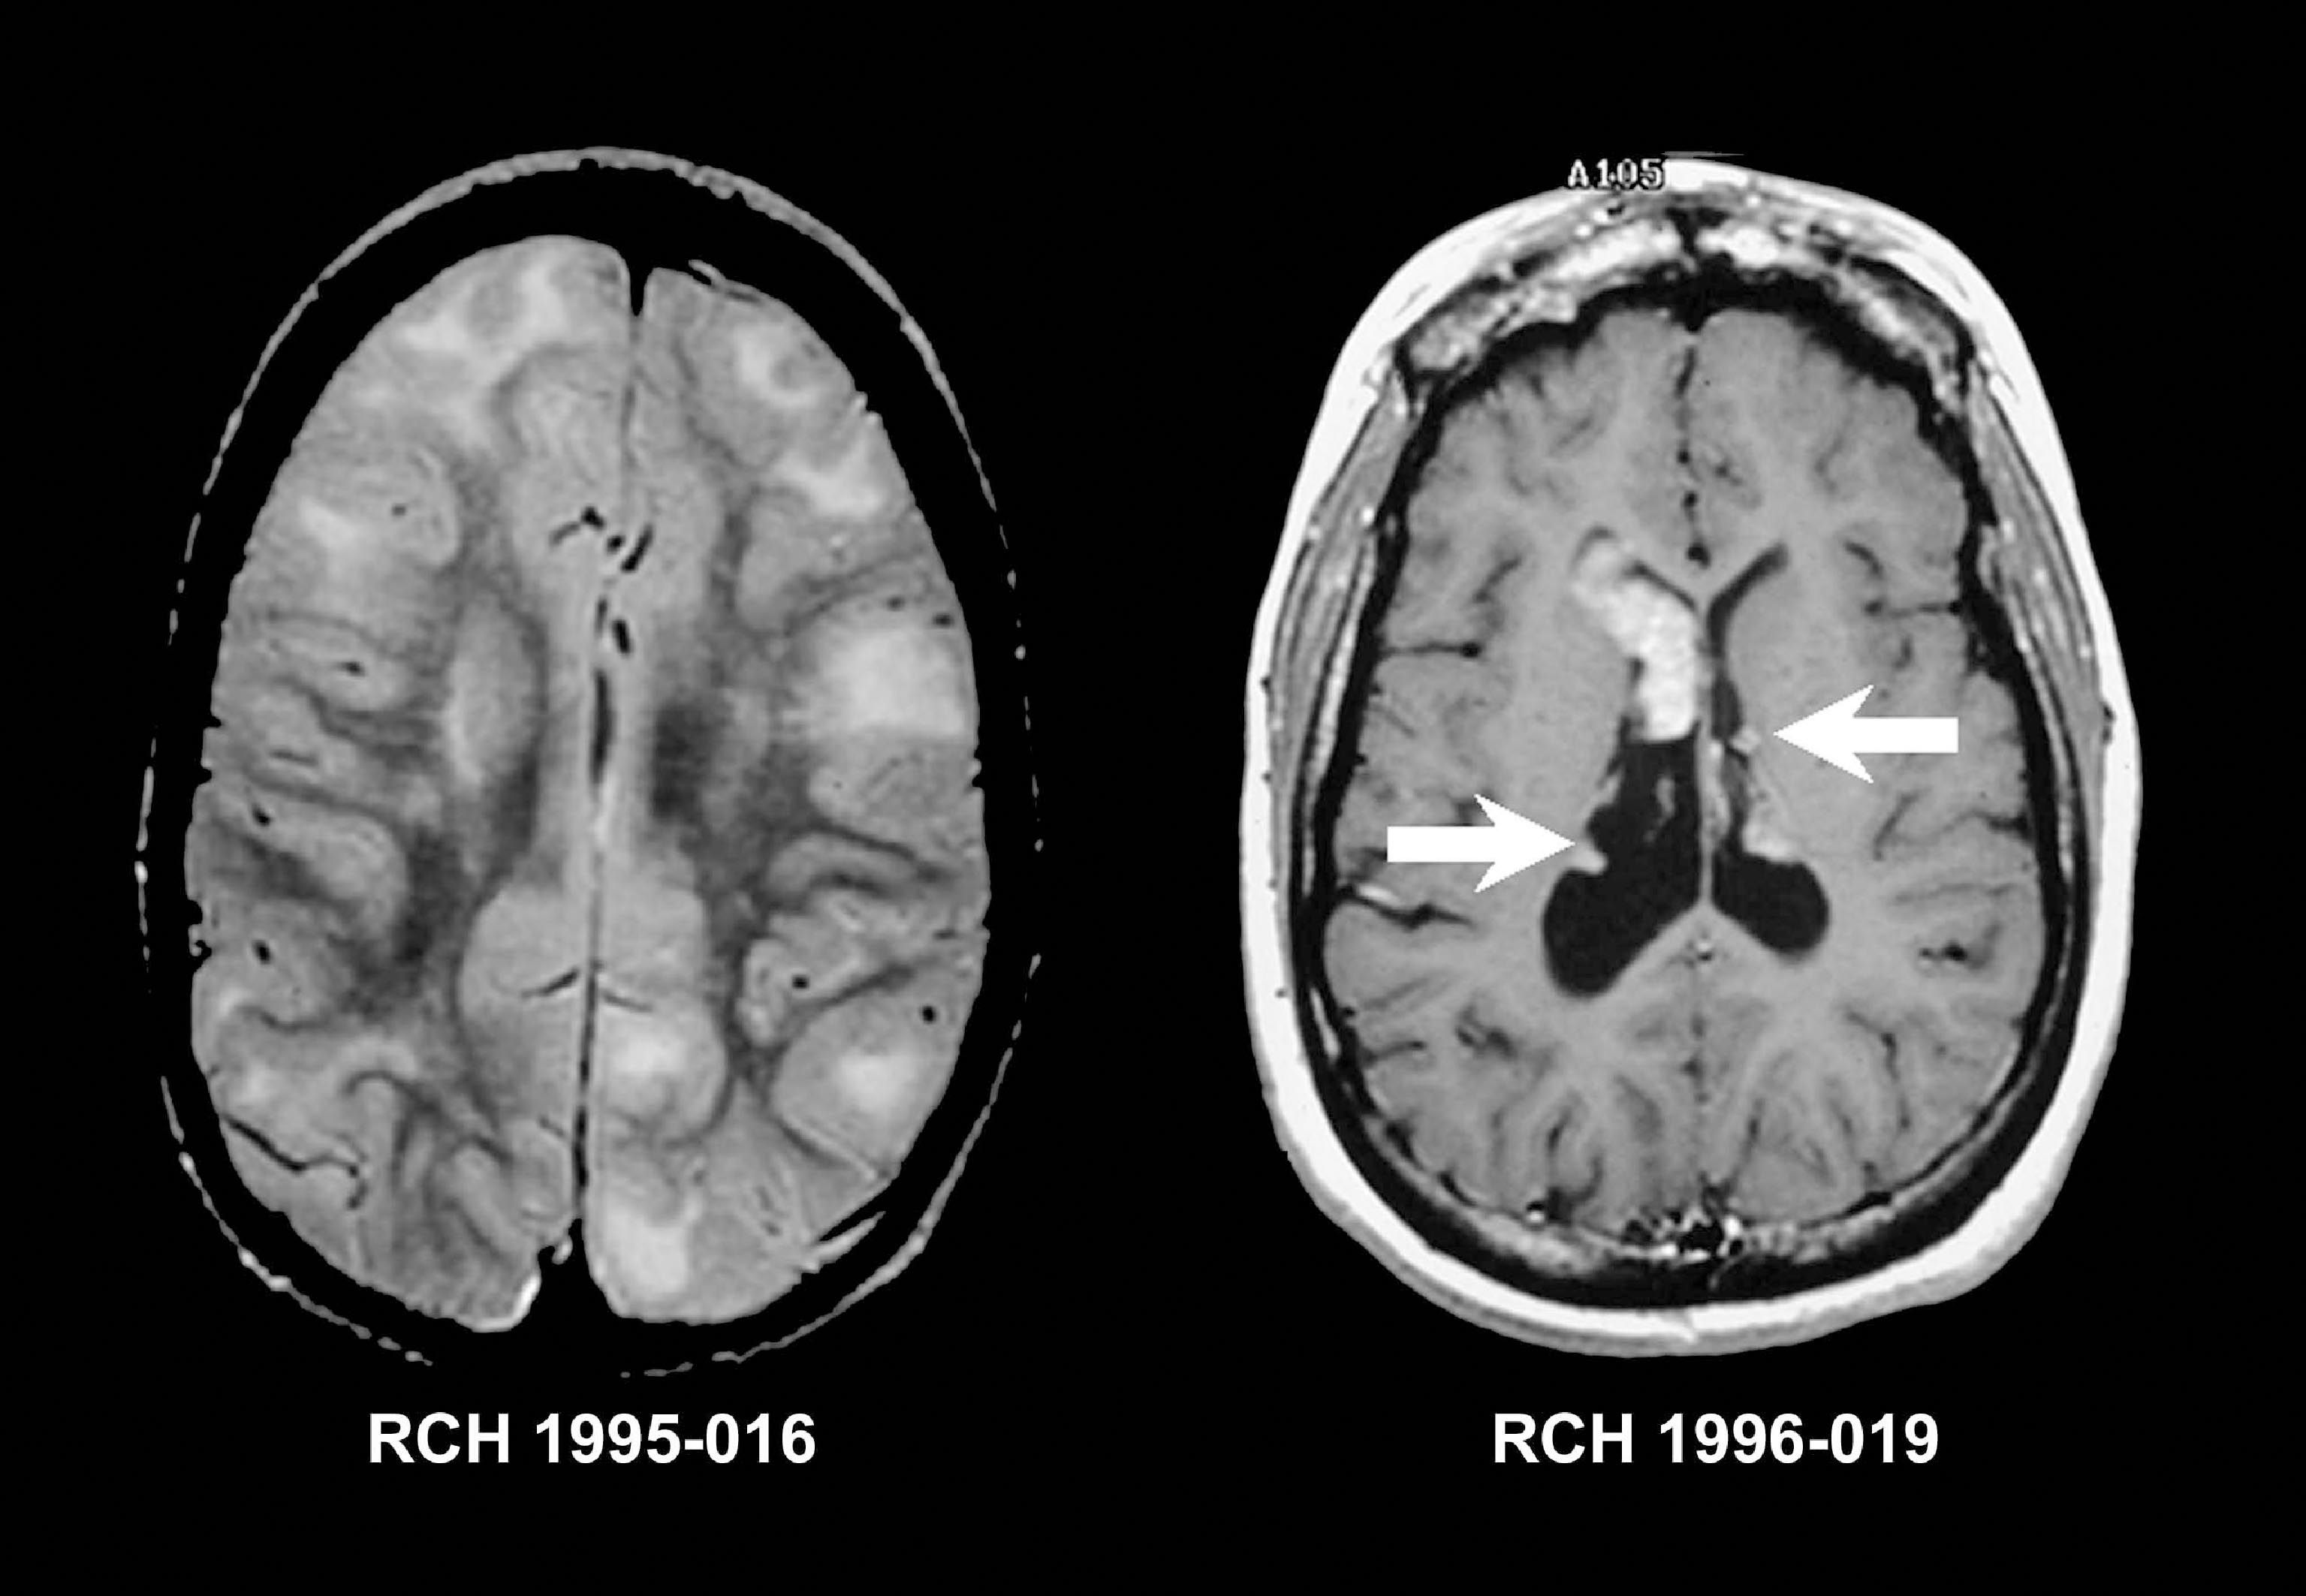

Understand how an MRI brain W WO contrast scan works. This diagnostic imaging procedure uses magnetic resonance technology with and without contrast dye to detect neurological conditions, tumors, and brain abnormalities. Learn what to expect during your exam, preparation tips, and why physicians use this detailed neuroimaging technique for accurate clinical diagnosis and effective treatment planning.